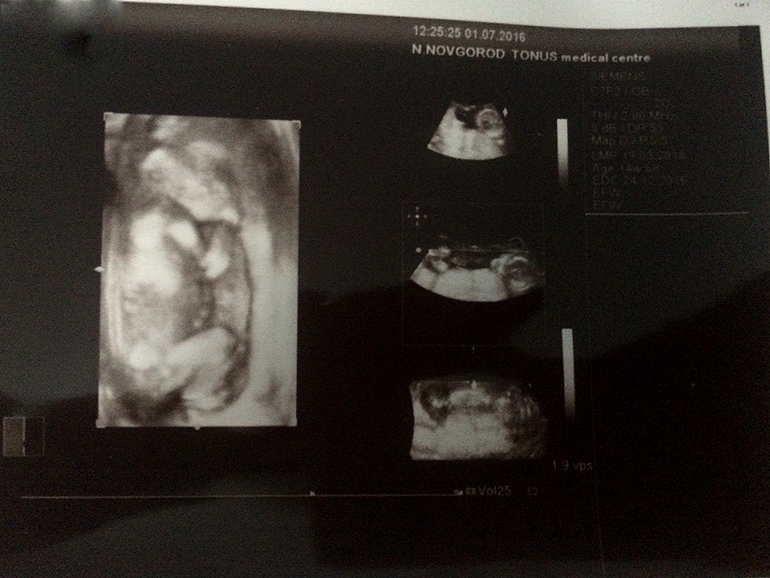

УЗИ в 15.0 недель. Психанула. Первое фото

Результаты: УЗИ, КТГ, доплера, скринингаВсю неделю живот странно себя вел, то есть я его чувствую. Психанула и пошла внепланово на платное УЗИ в клинику, в которой раньше только к хирургу ходила. Так вот. За 2,4 тыс. мне не написали и не сказали, как я поняла, вес и КТР. Пол даже посмотреть отказались.

Первую фотку, правда, сделали. Внизу фото результата УЗИ и плода